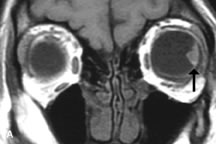

Dermoid cysts appear as rounded, well-defined lesions typically contiguous with an orbital bony suture. The high-intensity signal on T1-weighted images is attributed to the sebaceous-produced lipid contents (Fig. 18).31,50 Mucoceles may demonstrate a hypointense or hyperintense signal on MR images, depending on the concentration of proteinaceous or inflammatory fluid components. The integrity of the bony walls of the expanded sinus cavities cannot be assessed on MR as well as by CT.37,50,55,56 A high-signal intensity on Tl- and T2-weighted images is characteristic of orbital chronic hematic cysts because of the blood-breakdown products within the cysts.57

Fig. 18. A. T1-weighted, (B) T2-weighted fat-suppressed, and (C) T1-weighted fat-suppressed MR scans demonstrate a small dermoid cyst arising near the palpebral portion of the lacrinal gland (arrows). The lesion is similar in signal intensity to fat on the T1-weighted scan (A) consistent with a high adipose tissue content. The lesion shows fat-suppression and low signal intensity on the two fat-suppressed sequences (B and C) confirming its high lipid content.